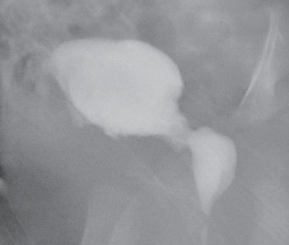

A 14-year-old girl came to the office with severe hip pain, which occurred after she attempted a cheerleading maneuver on a trampoline.